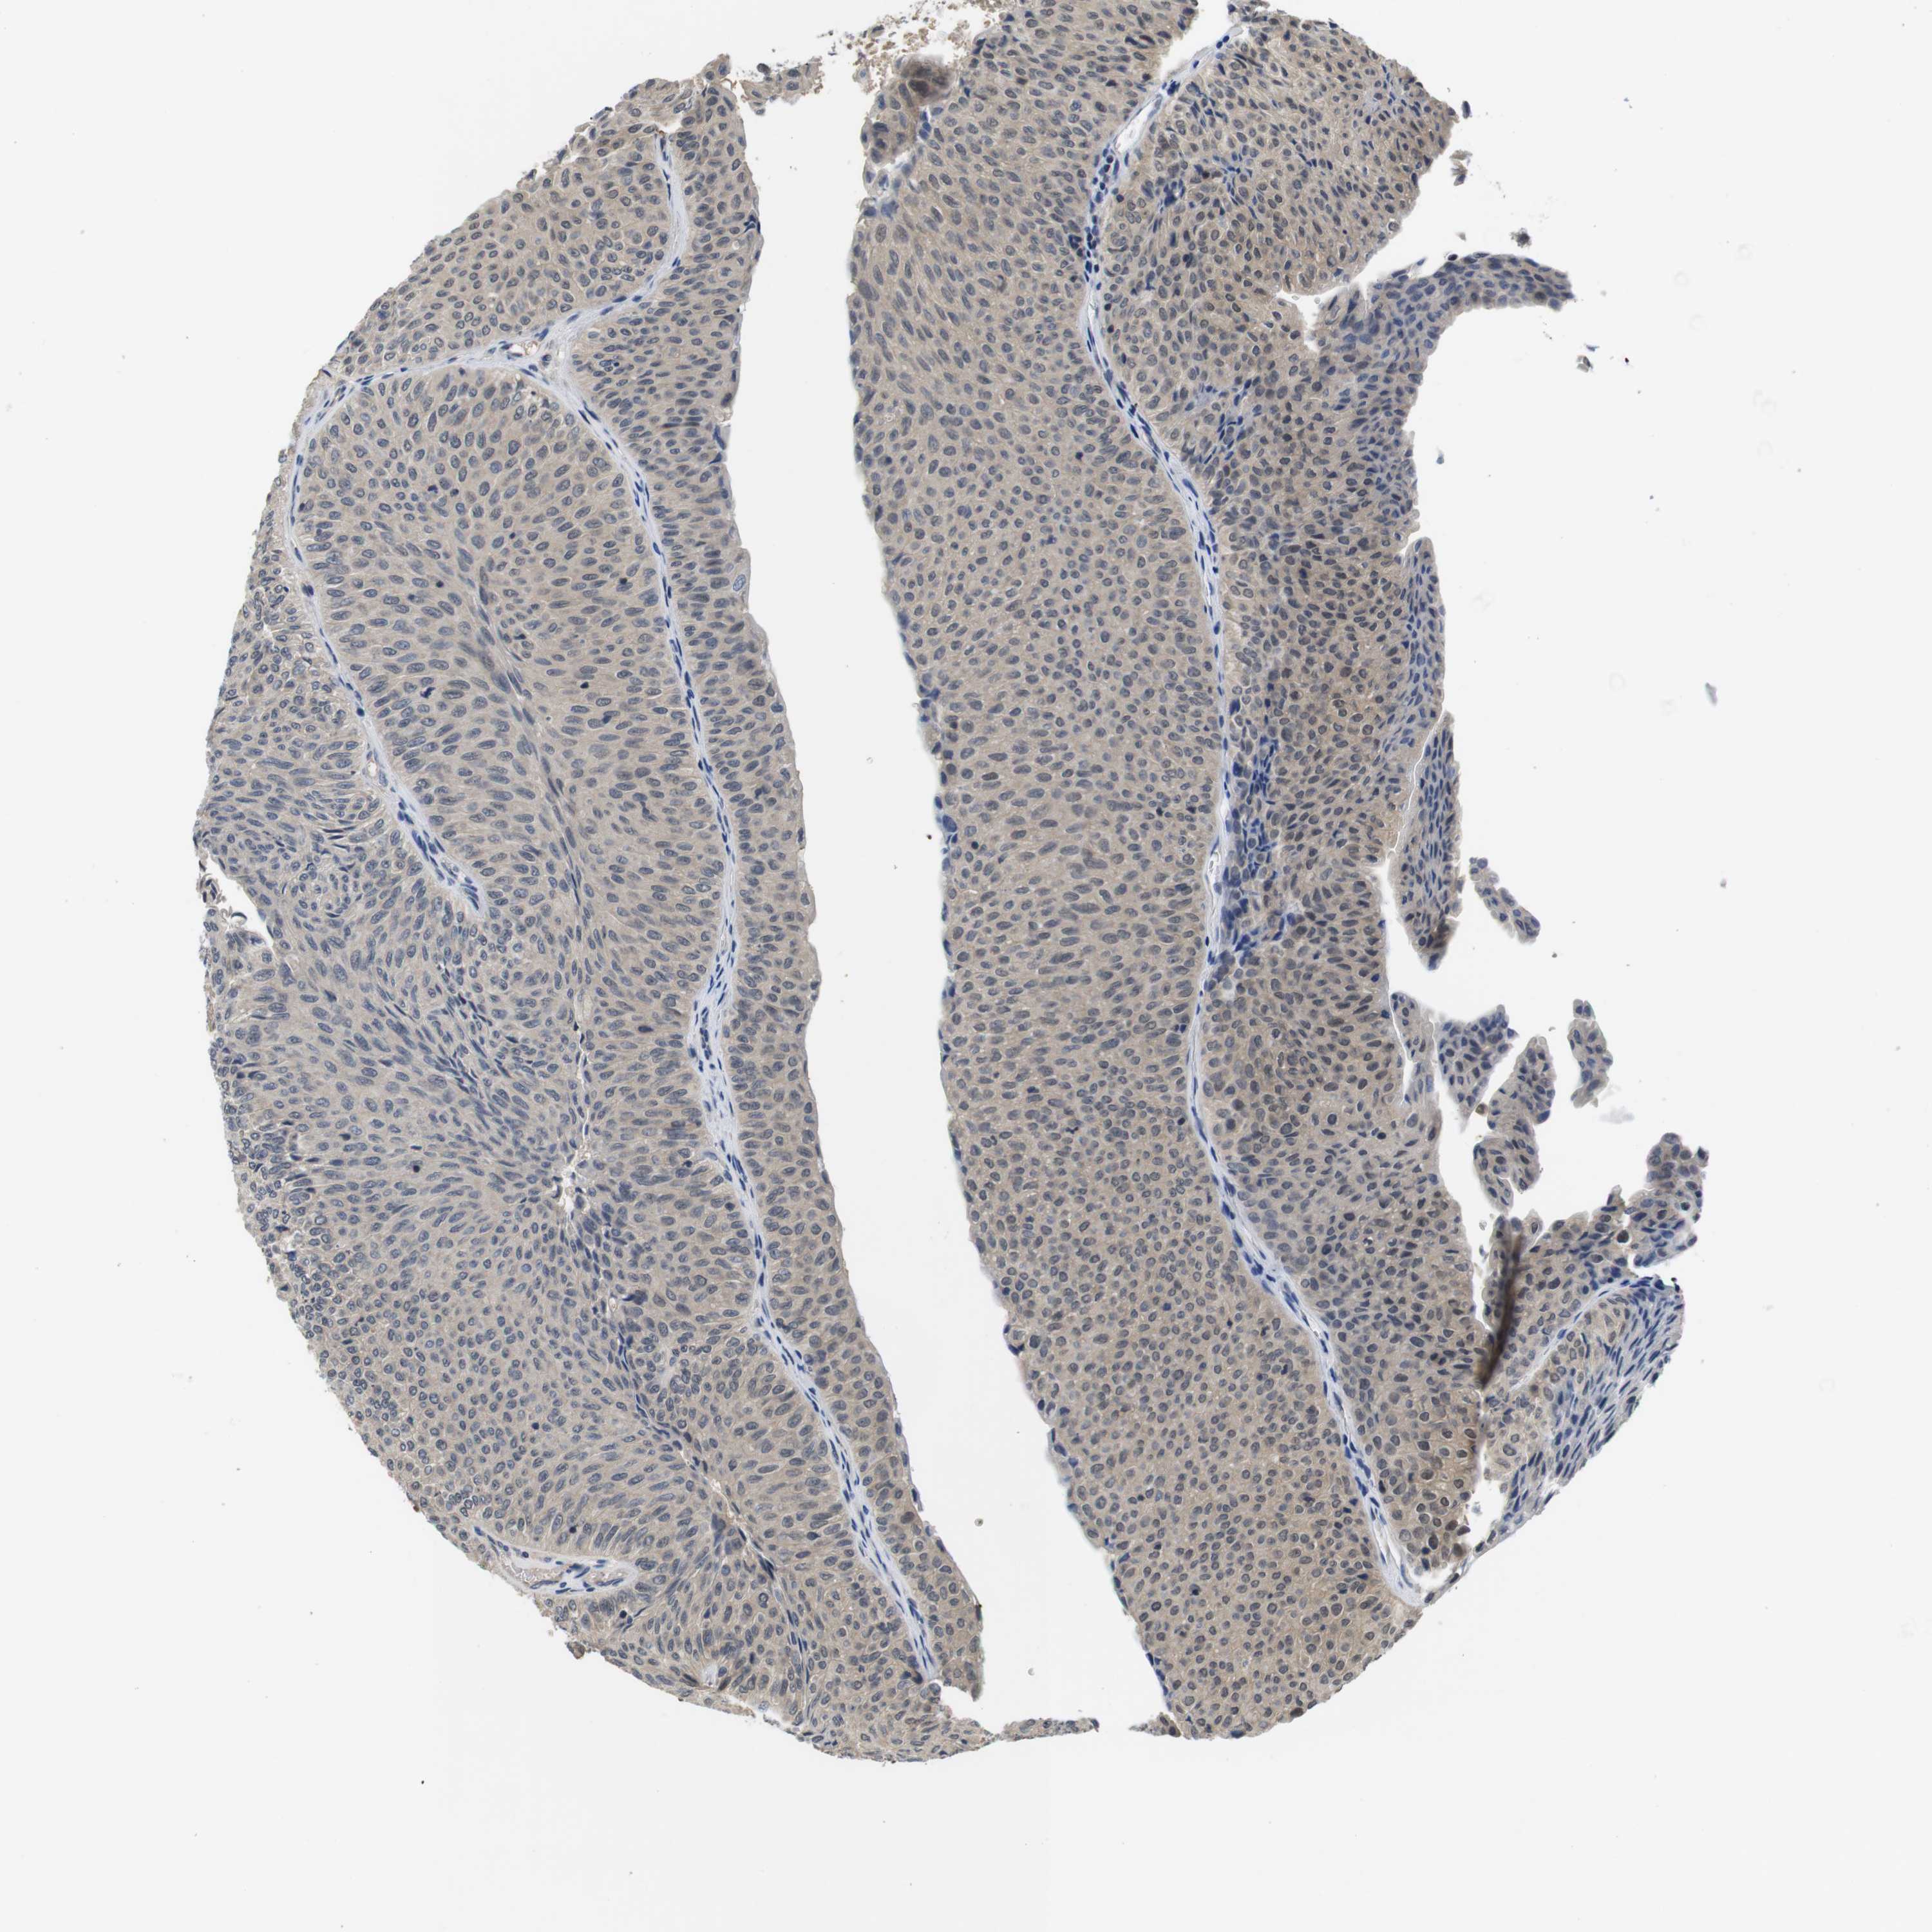

UROTHELIAL CANCER - Protein expressioni

A mouse-over function shows sample information and annotation data. Click on an image to view it in a full screen mode. Samples can be filtered based on level of antibody staining by selecting one or several of the following categories: high, medium, low and not detected. The assay and annotation is described here.

Note that samples used for immunohistochemistry by the Human Protein Atlas do not correspond to samples in the TCGA dataset.

Antibody stainingi

Antibody staining in the annotated cell types in the current human tissue is reported as not detected, low, medium, or high, based on conventional immunohistochemistry profiling in selected tissues. This score is based on the combination of the staining intensity and fraction of stained cells.

Each image is clickable and will lead to virtual microscopy that enables deeper exploration of all samples and also displays staining intensity scores, fraction scores and subcellular localization as well as patient and tissue information for each sample.

Antibody HPA001464

Antibody CAB010209

Urothelial carcinoma, Low grade